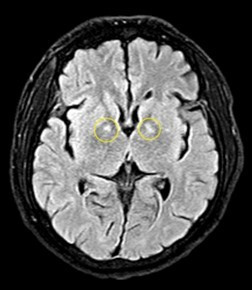

Hiện bệnh nhân nam có tổn thương não. Các bệnh nhân nữ tổn thương tim, suy tim, tiêu cơ tim và nguy cơ di chứng với tâm thần, thần kinh rất cao.

Hình ảnh tổn thương não của bệnh nhân nam - Ảnh BVCC

TS.BS Nguyên hội chẩn tổn thương não ở bệnh nhân - Ảnh BVCC